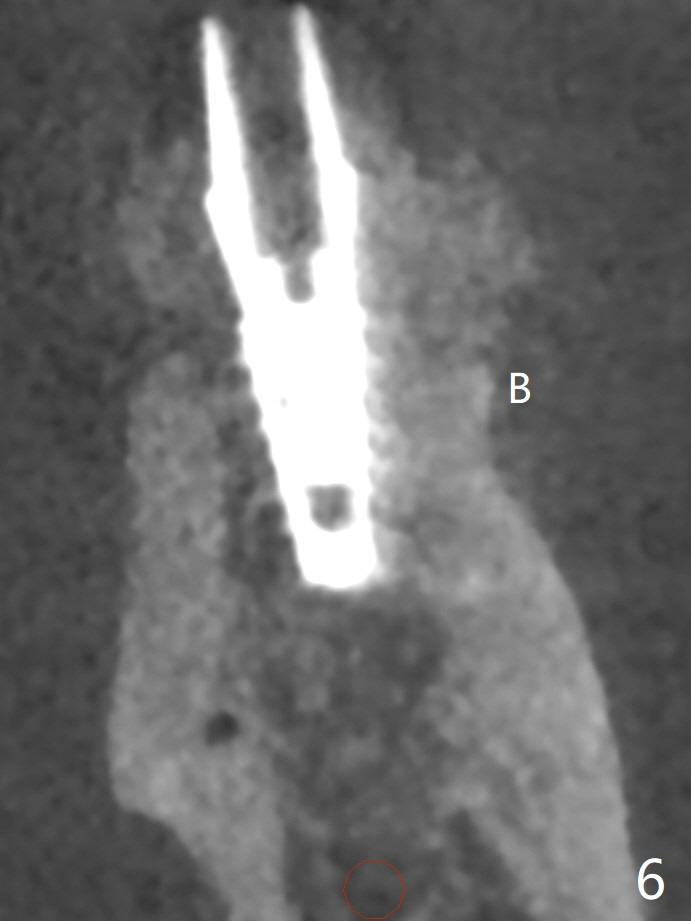

In spite of smoking reduction (1ppwk), the infection at #19, including buccal fistula (Fig.1 <) seems to be so severe that it affects pain threshold. Local anesthetics have to be added, including Bupivacaine IANB. When 4x10 mm drill is being applied, the patient feels pain. The plan is to use 4x11.5 mm drill as a final one. A 4x9 mm dummy implant is placed with 2.8 mm implant exposed (Fig.2 >), but it is subcrestal mesiodistally. Primary stability of a definitive 4.5x9 mm implant is satisfactory (Fig.3), but after initial bone graft, a 5x5.7(4) mm abutment is unable to be seated completely (<). Following 4.6 and 5.6 mm bone profile drills, the abutment remains incompletely seated (Fig.4). After fine turning, the abutment is fully seated; final round of bone graft (sticky bone) is placed mesiodistally (Fig.5 *) and buccolingually (Fig.6,7). It appears that there is tight fit between IBS implant and abutment. It is hoped that the excess bone graft with PRF is able to cover the coronal portion of the implant. If not, socket preservation should be done in this situation. In fact the implant is not placed lingual enough as compared to the design (Fig.6'). A 4.5 mm cortical drill should be used in a crown down fashion. In fact there is bone coverage coronally 5 months postop (Fig.8). Return to Prevent Molar Periimplantitis (Protocols, Table) No Deviation 12/14 Xin Wei, DDS, PhD, MS 1st edition 02/11/2020, last revision 06/30/2020